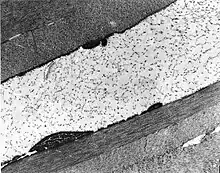

| The cornea is particularly opaque in the anterior stroma by slit-lamp biomicroscopy. | |

Congenital stromal corneal dystrophy (CSCD) is an extremely rare, autosomal dominant form of corneal dystrophy.[1] Only 4 families have been reported to have the disease by 2009.[2] The main features of the disease are numerous opaque flaky or feathery areas of clouding in the stroma that multiply with age and eventually preclude visibility of the endothelium. Strabismus or primary open angle glaucoma was noted in some of the patients. Thickness of the cornea stays the same, Descemet's membrane and endothelium are relatively unaffected, but the fibrils of collagen that constitute stromal lamellae are reduced in diameter and lamellae themselves are packed significantly more tightly.